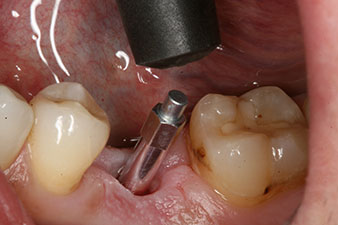

Figura 4: Poste de medición atornillado SmartPeg para determinar el cociente de estabilidad del implante con el módulo Osstell ISQ de W&H.

El torque en el momento de la carga mecánica fue de 43 Ncm. Asimismo, después de atornillar un poste de medición especial adaptado al sistema de implante (SmartPeg), el valor ISQ se determinó con la sonda del módulo Osstell ISQ de W&H.

Este módulo Osstell ISQ que se encuentra disponible como accesorio para la unidad Implantmed de W&H y se acopla al motor de implantes (véase figura 11). El valor ISQ adimensional fue de 64 justo en el momento de la inserción en la dirección bucovestibular y de 68 en la dirección mesiodistal (valor máximo = 100).